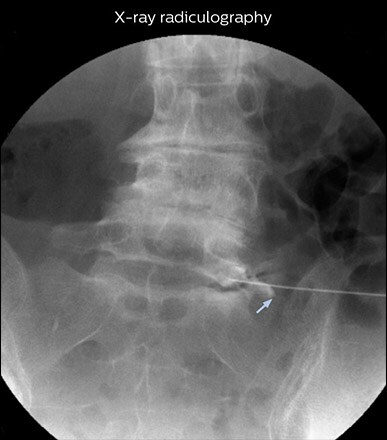

“Before NerveVIEW, diagnosis by MRI alone was sometimes difficult, unless there was a strong suspicion based on clinical symptoms,” says Shoji Yabuki, MD, DMSc, Orthopedic surgeon at Fukushima Medical University School of Medicine. “This is why we routinely perform selective lumbosacral radiculography (nerve root block) and x-ray in such cases. However, radiculography can only depict nerves as far as the contrast agent reaches. When a nerve is distorted by compression, the contrast agent will not pass through this compressed area, preventing us from evaluating the full nerve compression.”

“In such case, we would then browse through axial T2-weighted MR images slice by slice and mentally reconstruct the actual situation based on both radiculography and MRI. Fortunately, NerveVIEW can now very well show nerve courses and presence of nerve compression or edema in one single image series.”   “We have often seen NerveVIEW directly depict details of the nerve compression that were not observed by radiculography. Therefore, we think that with NerveVIEW we can reduce the number of invasive examinations, especially for some patients with lumbar plexus symptoms.”

“NerveVIEW can clearly show nerve courses and presence of nerve compression. However, when multiple abnormalities are seen, it can still be hard to determine which nerve is causing the symptoms,” says Dr. Yabuki. “In our experience so far, we see abnormal findings on NerveVIEW in about 70% of elderly patients. As the pain is usually caused by only one nerve, we thus need to find the exact corresponding nerve.”   “With a nerve root block, the patient's pain is improved by infiltration of local anesthesia directly around the nerve root considered to be responsible. Knowing such nerve root block findings prior to image interpretation, helps to easily recognize abnormal findings on NerveVIEW as well. In other words, without a priori knowledge, based on symptoms and/or nerve root block findings, we must be aware of the possibility of overdiagnosis.”